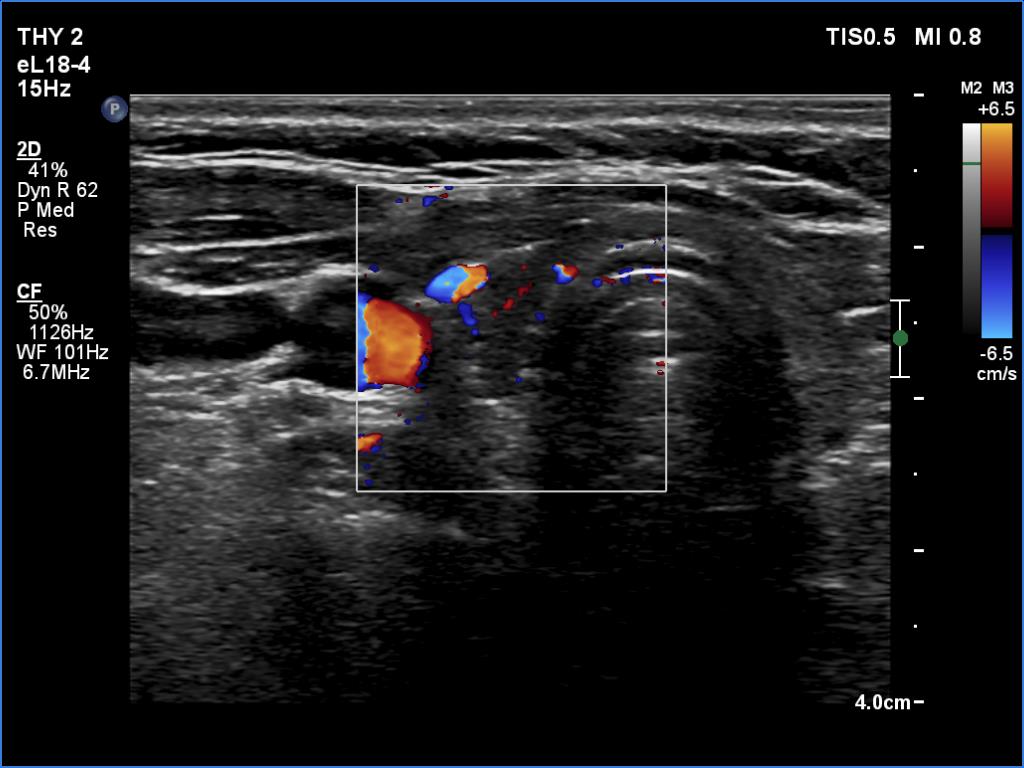

First examination (1st to 3rd rows of images):

Ultrasonography: The thyroid was echonormal. There were multiple hypoechogenic areas with ill-defined borders in both lobes. According to the hypoechogenic areas, the vascularization was practically absent.